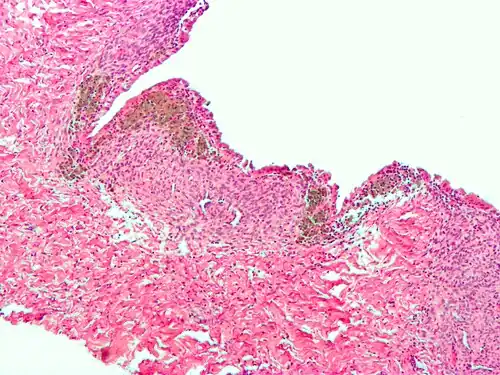

-

Endometriosis, abdominal wall

Endometriosis, abdominal wall -

Micrograph of the wall of an endometrioma. All features of endometriosis are present (endometrial glands, endometrial stroma and hemosiderin-laden macrophages).

Micrograph of the wall of an endometrioma. All features of endometriosis are present (endometrial glands, endometrial stroma and hemosiderin-laden macrophages).